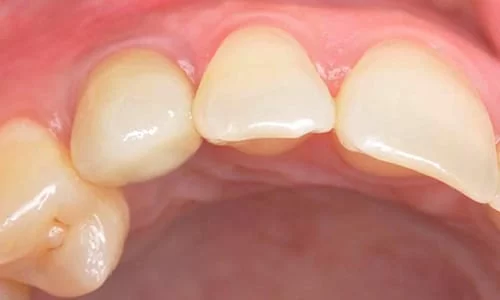

植牙假牙裝置後

患者本身來門診時,乳齒搖動度已相當大,僅殘根黏著於牙齦處,故並無任何咬合及飲食功能,對患者本身的生活造成了影響及困擾。且因乳牙本身型態過小、不佳並且搖動,以至於患者不敢露出牙齒笑,也間接影響了人際互動關係。

在植牙重建美觀及咬合功能後,對於病患來說,除了可以正常飲食之外,也對其自信心產生了極大的鼓勵。